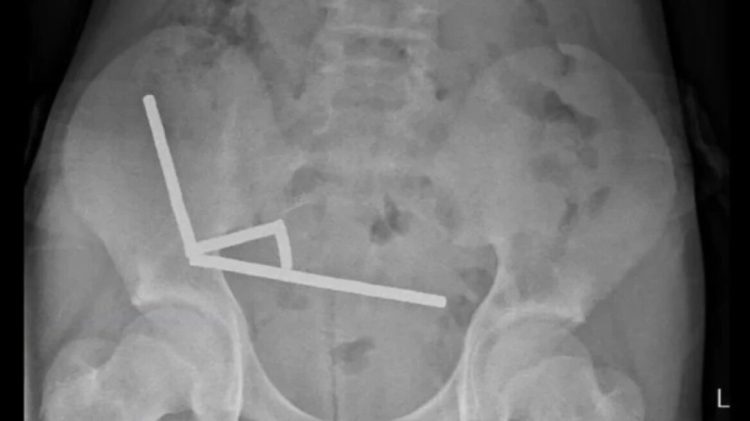

Το παιδί υπέφερε από έντονους πόνους στην κοιλιά για τέσσερις ημέρες πριν μεταφερθεί σε νοσοκομείο στο Βόρειο Νησί. Οι γιατροί εντόπισαν μέσω ακτινογραφίας ότι οι μαγνήτες είχαν σχηματίσει τέσσερις παράλληλες γραμμές μέσα στο έντερο, προσελκυόμενοι μεταξύ τους λόγω των μαγνητικών δυνάμεων.

Η πίεση που ασκούσαν οι μαγνήτες προκάλεσε νέκρωση σε τέσσερα σημεία του λεπτού και του τυφλού εντέρου. Οι χειρουργοί αφαίρεσαν τους μαγνήτες και τον κατεστραμμένο ιστό, ενώ το αγόρι πήρε εξιτήριο έπειτα από οκτώ ημέρες νοσηλείας.